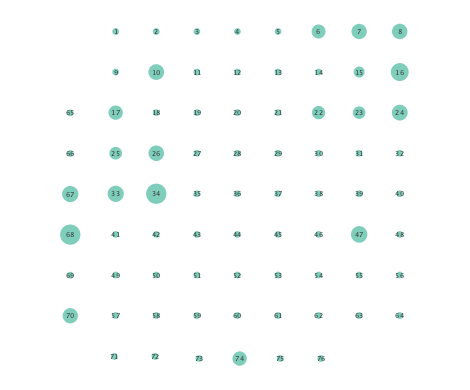

Figure 2 depicts networks inferred from different algorithms for both preictal and ictal intervals of the time series. The figure illustrates results obtained by the linear SVARM, and the K-SVARM approach with and without kernel selection. Each node in the network is representative of an electrode, and it is depicted as a circle, while the node arrangement is forced to remain consistent across the four visual representations. A cursory inspection of the visual maps reveals significant variations in connectivity patterns between ictal and preictal intervals for both models. Specifically, networks inferred via the K-SVARMs, reveal a global decrease in the number of links emanating from each node, while those inferred via the linear model depict increases and decreases in links connected to different nodes. Interestingly, the K-SVARM with kernel selection recovered most of the edges inferred by the linear and the K-SVARM using a polynomial kernel, which implies that both linear and nonlinear interactions may exist in brain networks. Clearly, one is unlikely to gain much insight only by visual inspection of the network topologies. To further analyze differences between inferred networks from both models, and to assess the potential benefits gained by adopting the novel scheme, several network topology metrics are computed and compared in the next subsection.

First, in- and out-degree was computed for nodes in each of the inferred networks. Note that the in-degree of a node counts its number of incoming edges, while the out-degree counts the number of out-going edges. The total degree per node sums the in- and out-degrees, and is indicative of how well-connected a given node is. Figure 3 depicts nodes in the network and their total degrees encoded by the radii of circles associated with the nodes. As expected from the previous subsection, Figures 3 (a) and (b) demonstrate that the linear SVARM yields both increases and deceases in the inferred node degree. On the other hand, the nonlinear SVARM leads to a more spatially consistent observation with most nodes exhibiting a smaller degree after the onset of a seizure (see Figures 3 (c) and (d)), which may imply that causal dependencies thin out between regions of the brain once a seizure starts.